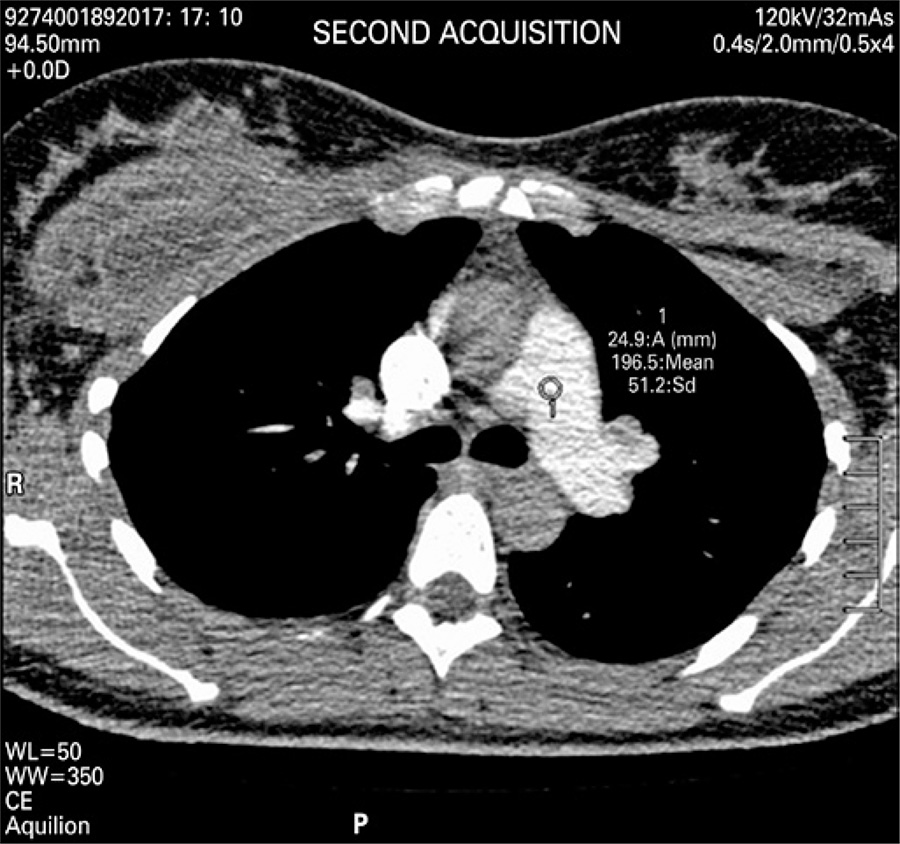

This was 37-year-old woman, 10 days after surgery, who underwent breast prosthesis replacement, abdominoplasty and liposuction. Upon admission, she was hemodynamically stable, febrile and reported constant pain on left hemithorax region, but without dyspnea.

An angio-CT of thoracic vessels was carried out. During intravenous injection of contrast agent, the patient was anxious and started crying during the exam. We believe that, a Valsalva maneuver was performed on inspiration apnea requested during the exam therefore causing an intrathoracic pressure that resulted only in a thoracic aortic contrast (). A new contrast agent was intravenously injected after apnea orientation, and the Valsalva maneuver was not requested, which resulted in precisely diagnostic images (). Two acquisitions were carried out using manual trigger when peak of pulmonary artery contrast occurred ( and ).